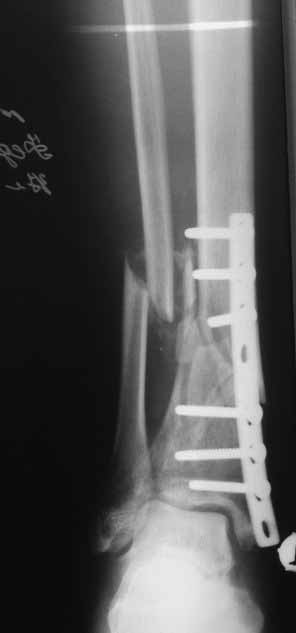

Это гипотрофический ложный сустав. Проблем видится несколько:

1. нарушение трофики в месте перелома.

2. после фиксации в аппарате Илизарова на рентгеногнрамме имеются признаки спицевого остеомиелила. В настоящи момент хотя свищей нет с мая 2011 нет опасно ли фиксировать голень стержнем?

На основании каких признаков Вы решили, что кость мертвая! Имеется гиперпластический ложный сустав, как результат недостаточно стабильной фиксации ан предыдущих этапах лечения. В данном случае необходимо решение следующих вопросов:

Место ложного сустава не выглядит гипертрофическим. Нет разрастания костной мозоли.

Закрыто все сделать не удасться. Фрагмент стержня нужно удалить, придется трепанировать кортикал и удалять фрагмент конец стежня. Свободная костная пластика - высой риск нагноения. Как вы думаете, может микрохирургически заместить дефект трансплантом из малоберцовой кости на сосудистой ножке это выход? В приложении статья о замещении костных дефектов трансплантатми на сосудистой ножке. описывают васкуляризованную костную пластику при ложных суставах.